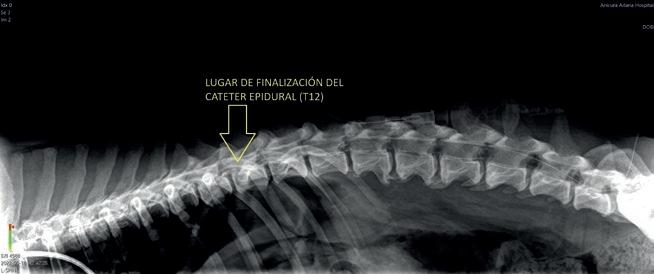

EN EL QR PODRÁS DESCARGARTE TODO EL MATERIAL DE LA CAMPAÑA 2024 NECESARIO PARA REDES SOCIALES:

• Contenidos editables para personalizar la campaña en tus redes sociales con adhesivos para tus reels, post, stories y WhatsApp, además de una guía de publicaciones,

• Guía práctica con nuevas ideas y consejos para elaborar post atractivos que enganchen